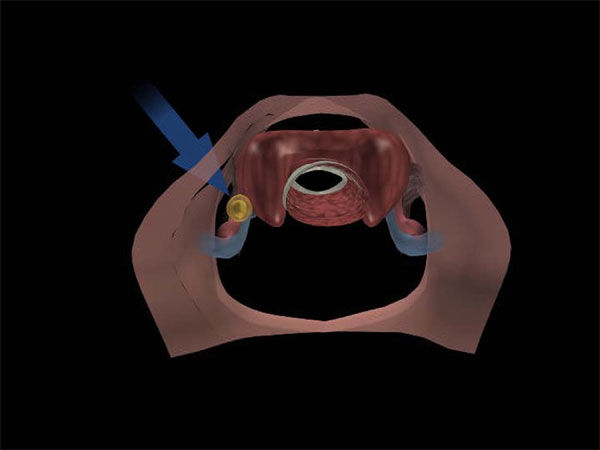

Major advances in surgical technique, particularly the advent of focused (minimally invasive) parathyroid surgery, have made parathyroid surgery a better option for increasing numbers of people worldwide

(Figure 8).

Growing awareness of the health benefits of parathyroid surgery has also driven this trend, which reflects a general shift in the risk-benefit ratio in favor of surgery.